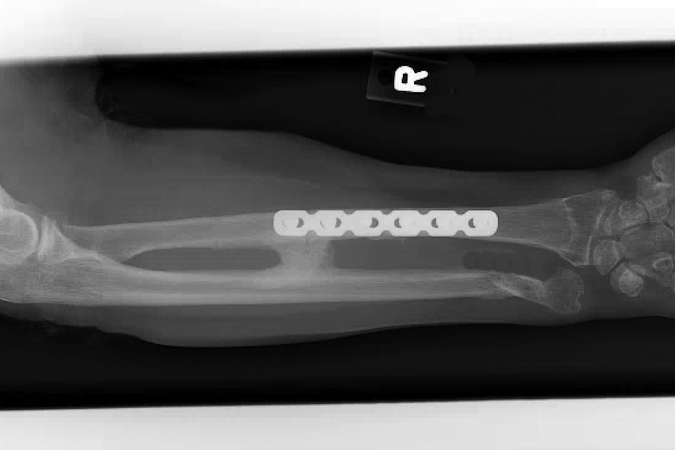

- Surgery is required in the majority of cases and first involves rigid fixation of the radius. This is followed by intraoperative assessment of DRUJ stability.

- Volar plate fixation

- Most common surgical approach

- Fixation may be more difficult when the fracture is in the distal third of the radius, where it may only be possible to insert two screws distal to the fracture line in these cases if using a 3.5-mm straight plate.1 Modern T-plates provide better fixation in the distal fragment by allowing additional screws in the distal fragment.